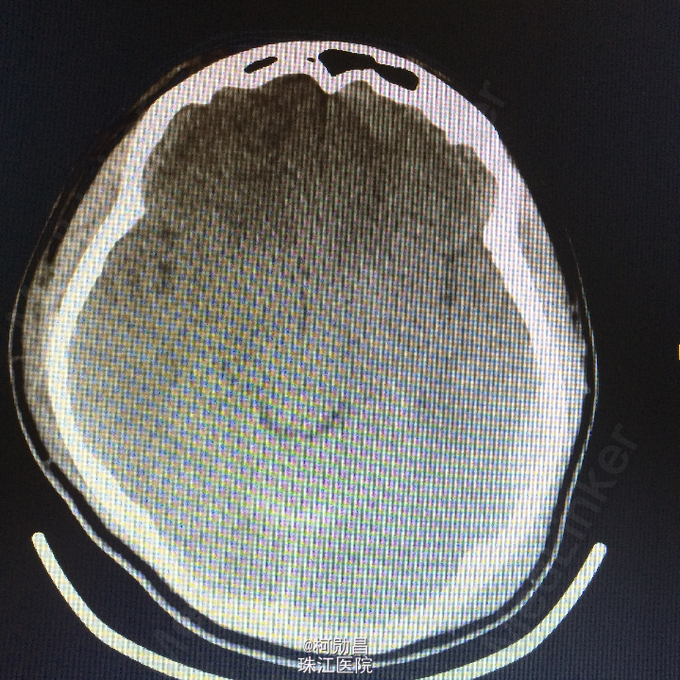

主诉:颅骨损伤后头痛、头晕2天 病史:患者于2天前骑摩托车时与机动车相撞,跌伤头部,至口角、眉弓处多处裂伤出血,左侧外耳道流血,当时患者无意识不清、肢体抽搐等。随即呼叫120送至医院。行头颅CT查示:左顶部硬膜下血肿,蛛网膜下腔出血,予相应治疗后病情稳定 。

查体:脑膜刺激征阳性 辅助检查:复查头颅CT及三维颅骨重建提示:血肿较前吸收,颅骨多发骨折,左额部较为明显

诊断:重型颅脑损伤,脑脊液耳漏、颅骨多发骨折